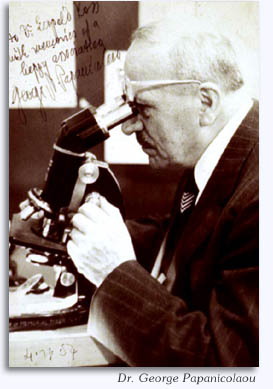

David B. Kaminsky, MD, FIAC

De wereld van de cytologie werd gedefinieerd door de opkomst van cervicale kankerscreening, bedacht en onder de aandacht gebracht door Dr. George Papanicolaou. Het bracht een ommekeer teweeg door de introductie van de fijne naald aspiratiebiopsie en vloeibare cytologie. De combinatie van deze twee voorziet in een krachtig diagnostisch hulpmiddel dat moleculaire en ondersteunende onderzoeken naar oncologische en infectueuze ziektes vergemakkelijkt. Beide vertegenwoordigen de huidige praktijknorm. Deze combinatie is de versterking van de basis voor moderne cytopathologie en is onmisbaar.

Fijne naald aspiratiebiopsie [FNAB] komt oorspronkelijk uit Stockholm, waar het werd ontwikkeld in het Karolinska en Radiumhemmet door de pioniers Franzen, Zajicek en Esposti, wiens oorspronkelijke werk, ondersteund door biopsiegegevens, bevestigde dat criteria voor celdiagnose betrouwbaar waren voor weefselpatronen en dat het naaldonderzoeksinstrument een praktisch diagnostisch hulpmiddel was dat minimaal invasief, weefsel-equivalente informatie kon leveren.